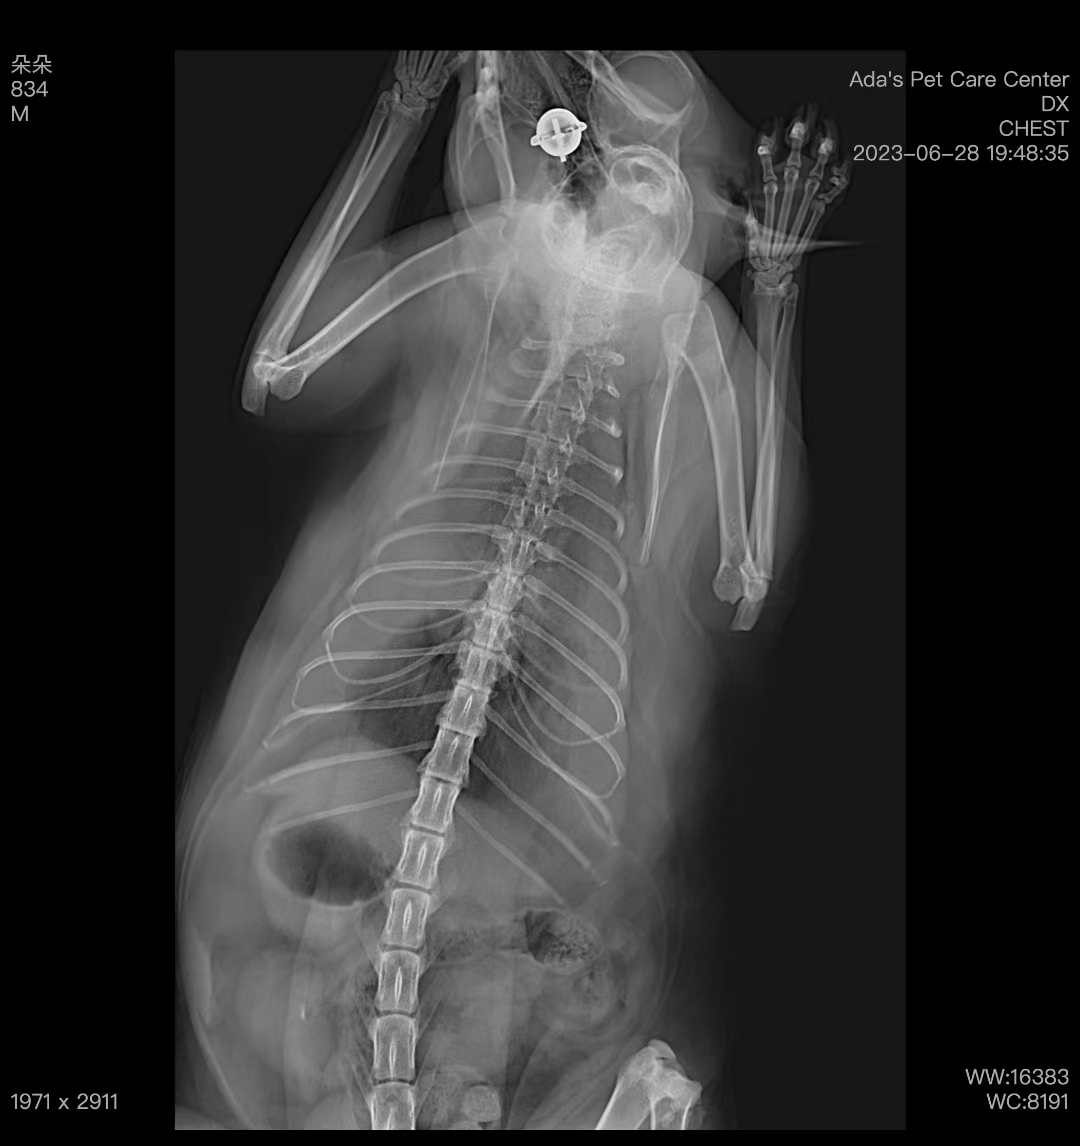

猫咪刚到医院时反应很差,呼吸困难,舌头发紫。吸氧后,呼吸情况稍微缓解。拍了胸部X光,结果显示胸腔里有明显的积液。我们做了胸腔穿刺,抽出了200ml乳黄色的积液,化验后确定是乳糜胸。